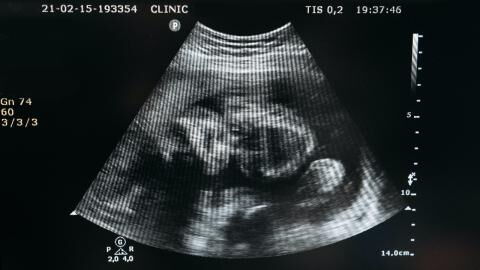

Whilst on their walk, the two women found a plastic box near a bench. So far, nothing too shocking. But when they examined the contents, they were shocked. As soon as they removed the lid, they saw that in the container was a human foetus.

According to initial information, as reported by Le Parisien, the investigation has been entrusted to the Évry/Corbeil police station. It is believed to be a foetus of about four months. An autopsy will be carried out by the investigators to try to determine the causes of its 'death.' The Evry public prosecutor declared:

The examination will make it possible to know whether or not there was the intervention of a third party in the death. The legal questions will come later.